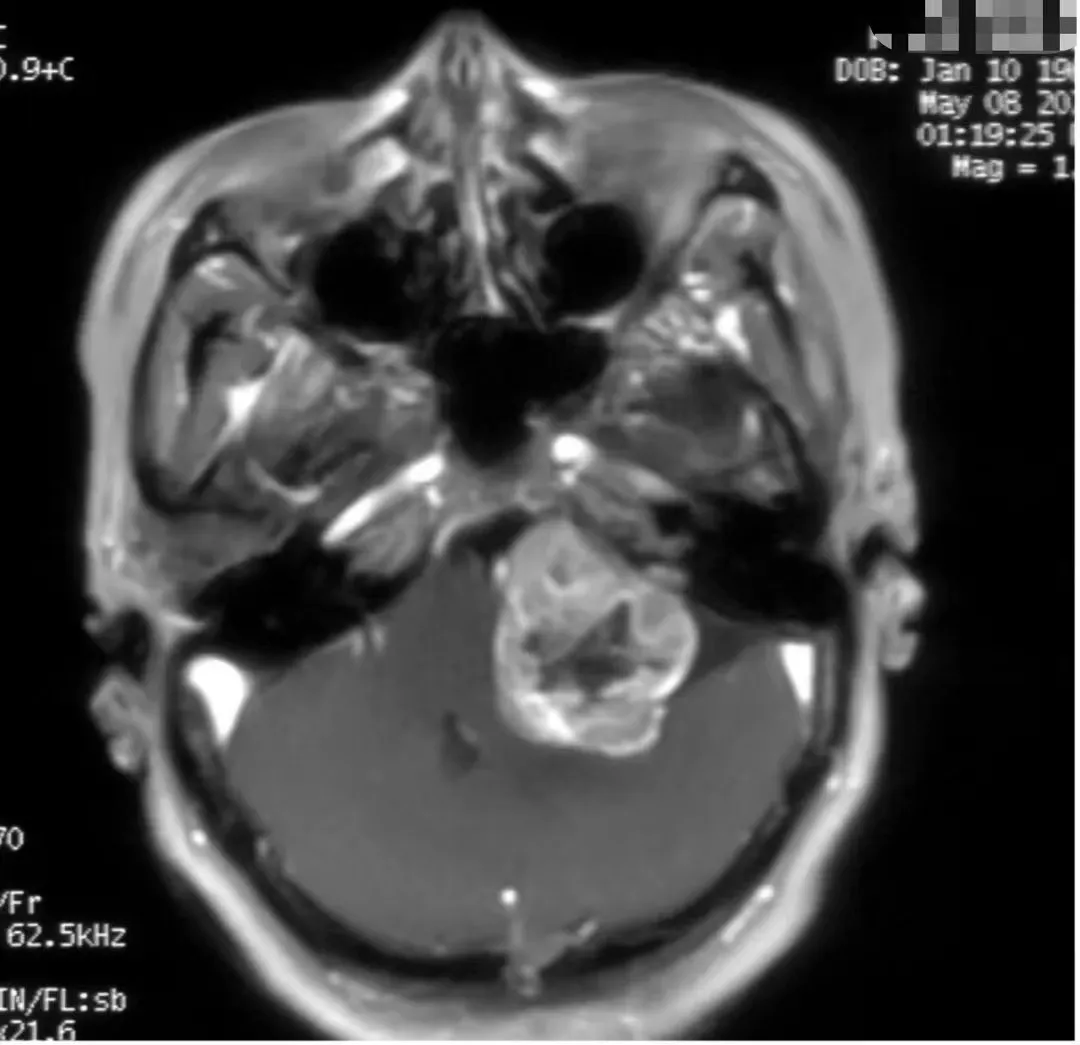

1000 Auditory Neuromas (Preoperative NMR)

The 1,000 acoustic neuromas have different sizes, textures, blood supply and adhesions, which indicate different surgical difficulties.